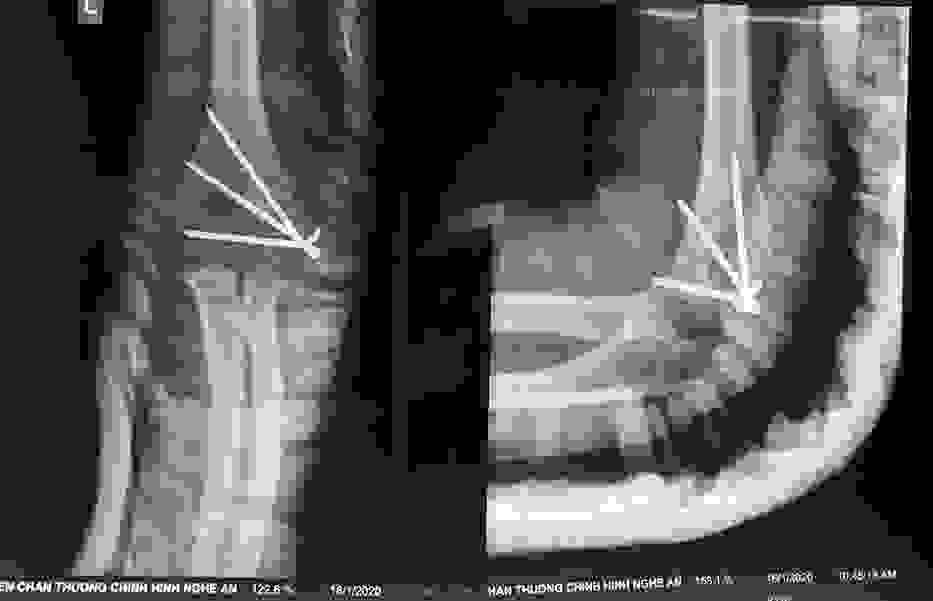

Phẫu thuật thành công ca bệnh hiếm gặp...khớp giả bẩm sinh xương chày

26/06/2019 17:00

Đã xem: 3523

Bệnh viện Chấn thương- Chỉnh hình Nghệ An, vừa phẫu thuật thành công cho bệnh nhi khớp giả bẩm sinh xương chày